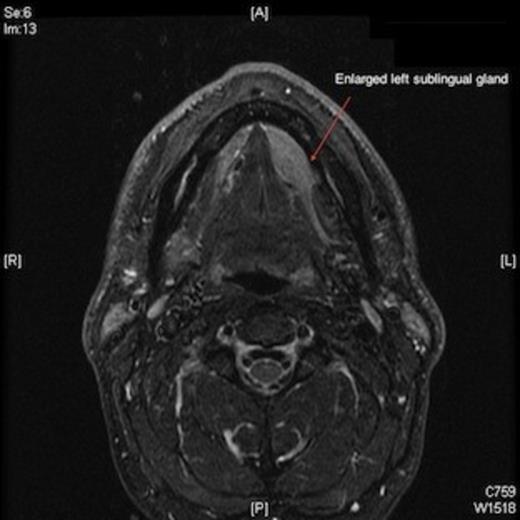

The clinical impression was of an enlarged sublingual gland, and so a fine needle aspiration was carried out. The cytology report confirmed salivary gland cells, some of which were enlarged. In view of this, a magnetic resonance imaging scan was ordered which confirmed a left anterior floor of mouth mass of 3 x 1 cm, (figures 1 and 2). Interestingly there was also a missing ipsilateral submandibular gland. The remaining major salivary glands were of normal appearance and dimensions.

Magnetic resonance imaging scan showing enlarged left sublingual gland.